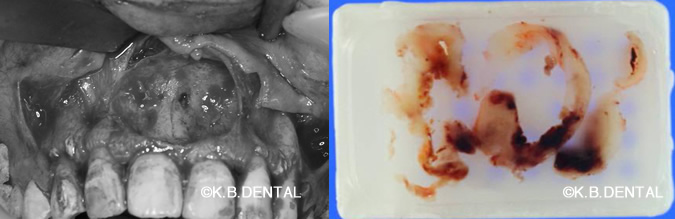

セメント質骨形成線維種

40代女性の右下顎角部に生じた良性腫瘍。特徴として発育緩慢で顎骨に無痛性の膨隆をきたし、皮質骨の菲薄化が見られるようになります。

神経と血管の管(下顎管)まで波及し、神経麻痺を主訴にご来院されました。今回は病巣部の歯牙を抜歯して同時に腫瘍を摘出し、一部健常部まで拡大して顎骨を切除しました。

術中は一部神経と動脈を巻き込んでいるため出血をコントロールしながら行います。

病理組織初見の特徴として以下が挙げられます。

- 細胞成分に富む線維性結合組織が増生する中にセメント質様ないし骨様の硬組織形成がみられる。

- 形成された硬組織周囲には骨芽細胞様細胞の縁取りが認められる。

- 周囲の既存骨との境界が明瞭。

静脈麻酔による日帰り手術で総額約20~25万円(保険適用外)